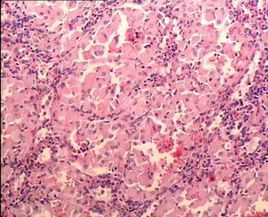

骨髓形態學檢查

大多數戈謝病患者骨髓形態學檢查能發現特徵性細胞即“戈謝細胞”,該細胞體積,細胞核小,部份胞質可見空泡。但該檢查存在假陰性及假陽性的情況。 假陰性: 即當未查見戈謝細胞時,仍不能否定患有戈謝病,需要通過葡萄糖腦苷脂酶活性檢測進行確診。假陽性:骨髓中的單核巨噬細胞等會吞噬細胞碎片或脂質代謝產物,形成與“戈謝細胞”相似的“類戈謝細胞”,在慢性髓性白血病、地中海貧血、多發性骨髓瘤、霍奇金淋巴瘤、漿細胞樣淋巴瘤中都可能出現這種“類戈謝細胞”。因此,當骨髓中查見“戈謝細胞”時, 應高度懷疑戈謝病,但並不能確診戈謝病,需在鑑別區分其他疾病的同時,進一步做葡萄糖腦苷脂酶活性測定。